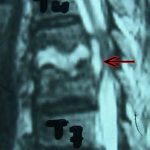

Εικ. 3: Μαγνητική τομογραφία της Θ.Μ.Σ.Σ. οβελιαία τομή, ακολουθία Τ1 & Τ2

Παρατηρούμε την αλλοίωση του σήματος σε όλες τις ακολουθίες, ενδεικτικό της ύπαρξης λοιμώξεως στο μεσοσπονδύλιο δίσκο και εκατέρωθεν αυτού στα σπονδυλικά σώματα. Είναι εμφανής η ύπαρξη επισκληριδίου αποστήματος στο σύστοιχο επίπεδο Θ5-Θ6 (ζ,η)